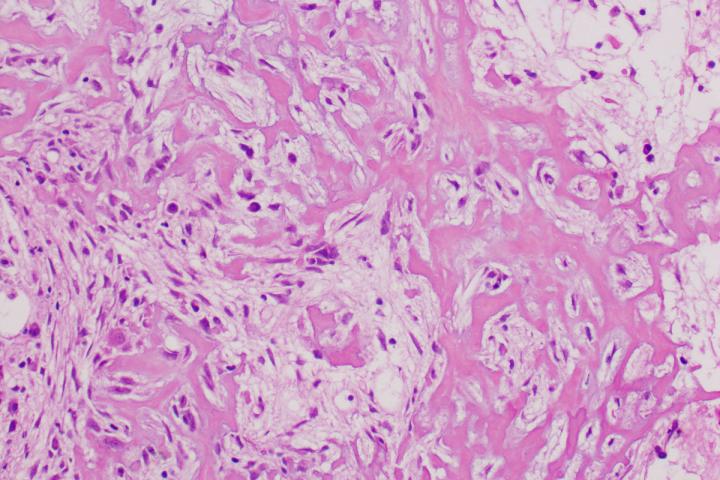

image: A new study from Washington University School of Medicine in St. Louis suggests that a two-drug combination targeting a tumor's energy sources could be as effective and less toxic than methotrexate, a long-used chemotherapy drug often given in high doses to treat osteosarcoma, a bone cancer. Shown is a cross section of osteosarcoma.

An innovative approach to treating bone tumors - starving cancer cells of the energy they need to grow - could one day provide an alternative to a commonly used chemotherapy drug without the risk of severe side effects, suggests a new study from Washington University School of Medicine in St. Louis. Studying human cancer cells and mice, the researchers said that a two-drug combination targeting a tumor's energy sources could be as effective and less toxic than methotrexate, a long-used chemotherapy drug often given in high doses to treat osteosarcoma, a bone cancer.

Osteosarcoma is the most common tumor of the bone in adults and children. It accounts for about 4% of all pediatric cancers and more than half of all pediatric bone cancers. Standard treatment for osteosarcoma includes surgery, radiation and a cocktail of chemotherapy drugs including high-dose methotrexate, which can cause liver and kidney damage.